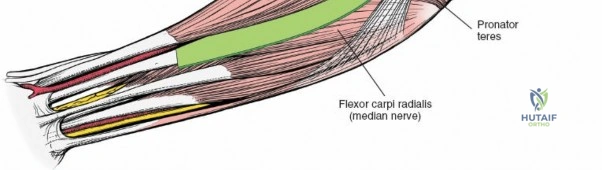

The anterior approach to the radius is an elegant example of utilizing true internervous planes to achieve deep exposure without denervating musculature. Distally, the internervous plane lies between the brachioradialis muscle (innervated by the radial nerve) and the flexor carpi radialis muscle (innervated by the median nerve). Proximally, the plane transitions to lie between the brachioradialis (radial nerve) and the pronator teres muscle (median nerve). Exploiting this plane allows the surgeon to mobilize the entire lateral muscular compartment (the "mobile wad" comprising the brachioradialis, extensor carpi radialis longus, and extensor carpi radialis brevis) away from the anterior flexor compartment.

To confirm the correct plane, look for the superficial branch of the radial nerve. This sensory nerve runs on the undersurface of the brachioradialis muscle. Once the true medial edge of the brachioradialis is found, develop the plane between it and the pronator teres (proximally) or the flexor carpi radialis (distally). Retract the brachioradialis laterally, taking care to keep the superficial radial nerve attached to its undersurface to protect it from traction injury.